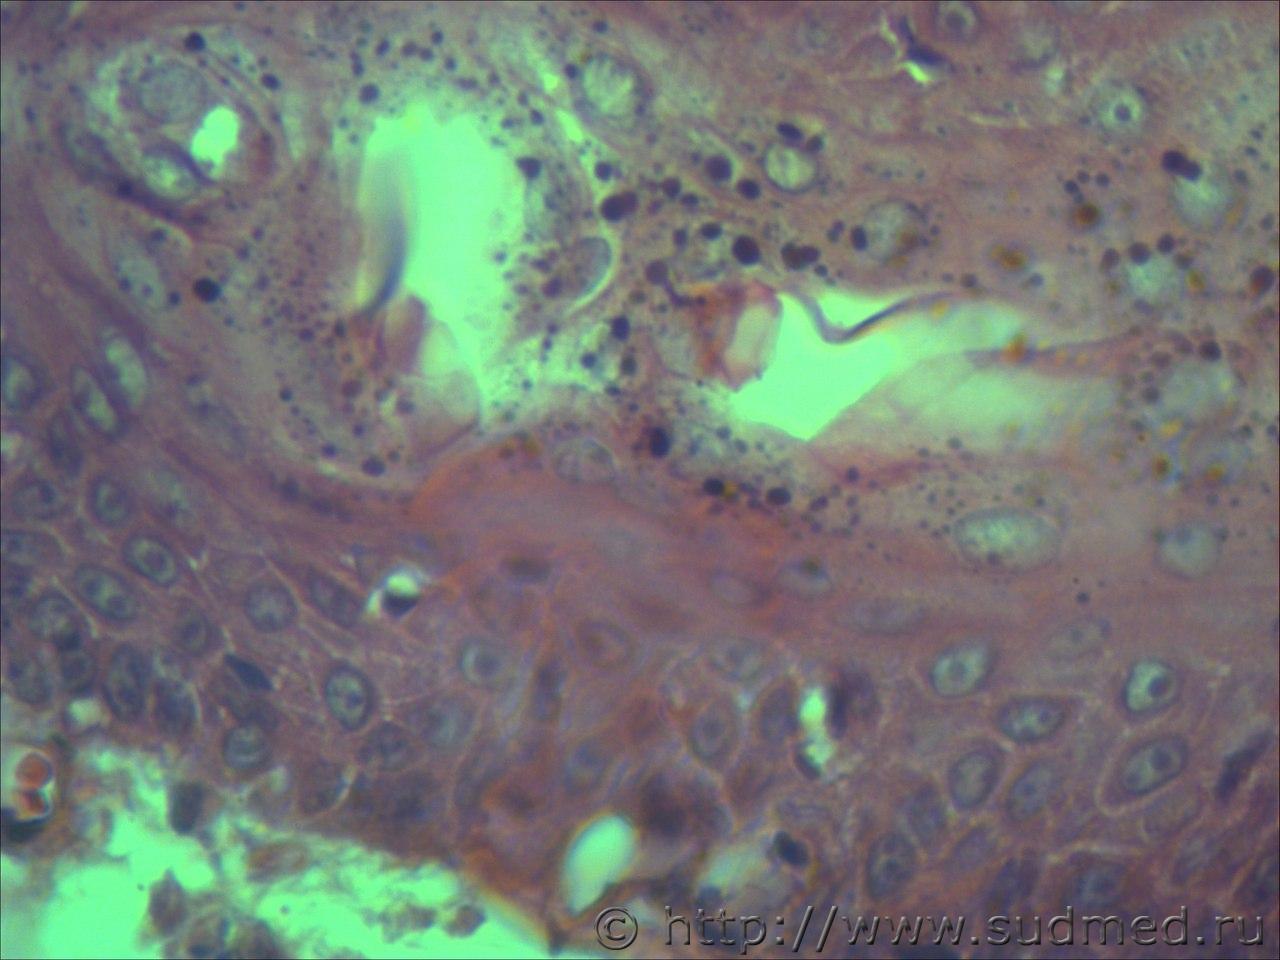

вижу что тяжи клеток эпидермиса проникающие в глубокие слои кожи и подлежащие ткани. Размеры клеток варьируют, слабовыраженное ороговение отдельных клеток, обильный воспалительный инфильтрат, пласты эпителиальных клеток в виде гнезд отделяются от эпидермиса. Склонен к ПКР

Попробую предположить,что на фото плазмоцитома и псевдокарциноматозная гиперплазия.